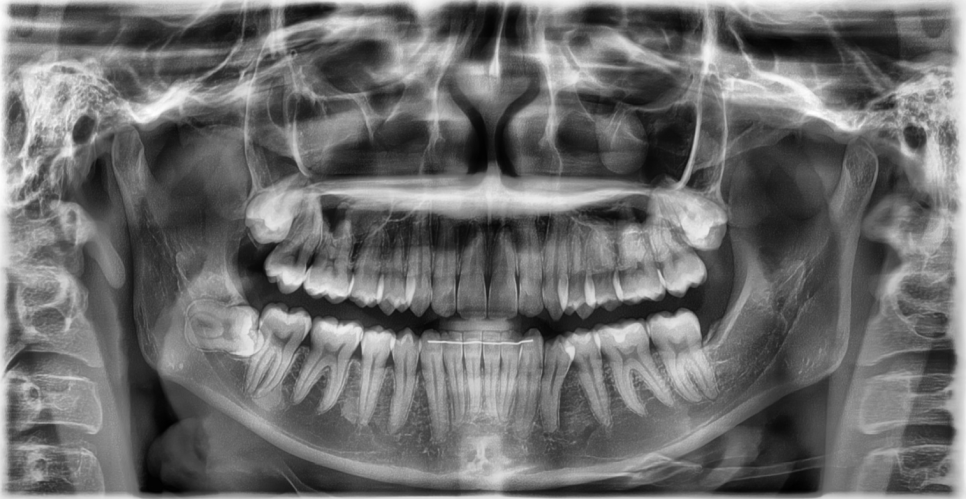

Wisdom teeth are located at the very back,

deepest part of the mouth.

A toothbrush does not reach them well,

food gets stuck easily,

and cavities often progress without the person noticing.

In particular, if it is an impacted wisdom tooth,

or one lying at an angle,

it often affects the molar in front of it as well.

The actual condition of the tooth,

its position inside the gum,

the distance from the nerve,

and even the range used when smiling or chewing

all need to be checked directly for an accurate judgment.